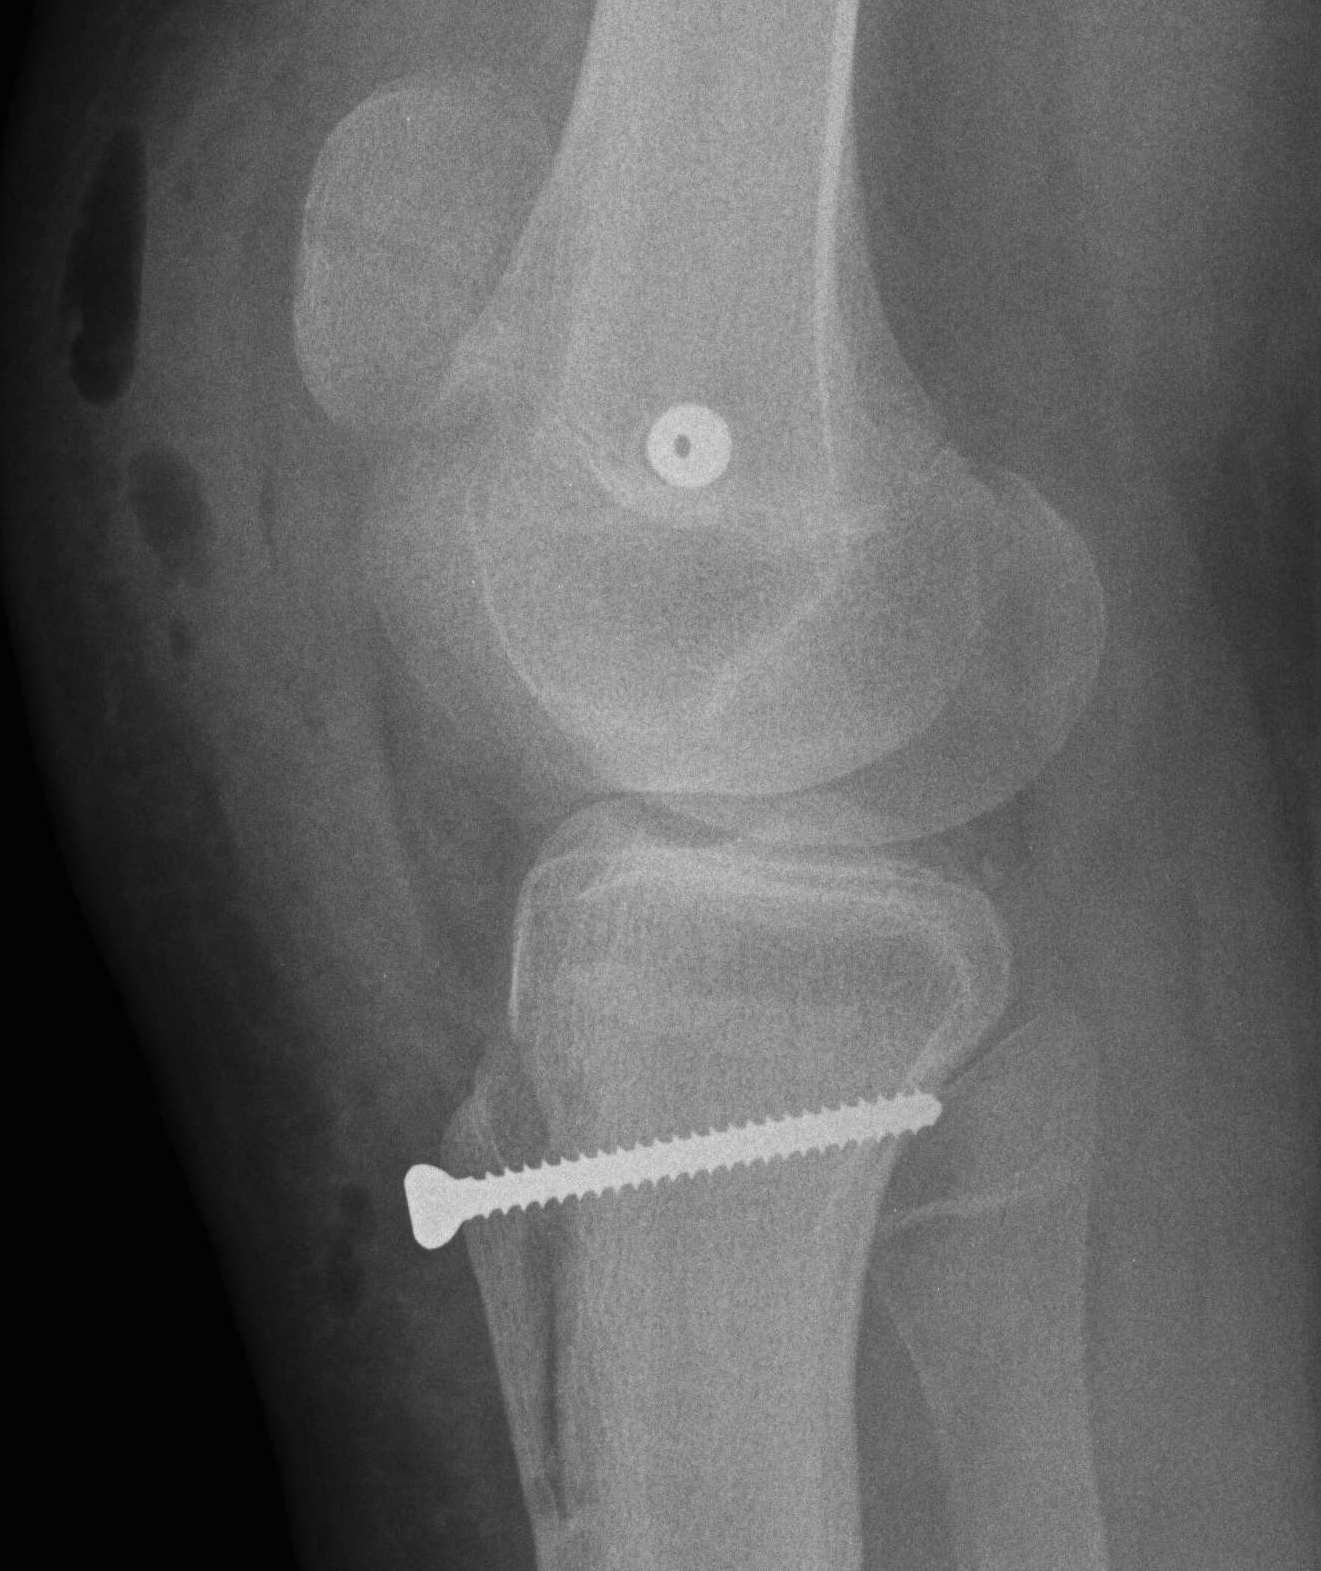

2. Perform TTT (if TTTG > 20)

- incision over TTT

- medialise at least 1 cm

- ensure some element of Fulkerson / anteriorise

- can distalise if patella alta

- secure with screws (2 x small fragment usually sufficient)

- reassess stability